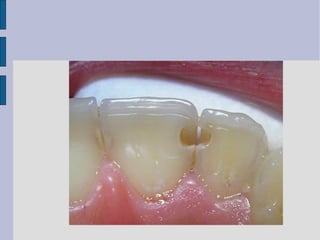

Class IV Tooth Preparation

 preoperative assessment of

occlusion is very important

(placement of margin in noncontact

areas)

 shade selection is more difficult

 preparation is similar to Class III

except that the preparation for class

IV is extended to the incisal angles

BEFORE AAFFTTEERR

Before the restoration

procedure.

After restoring with Composite

Resin Material

class iv direct composite